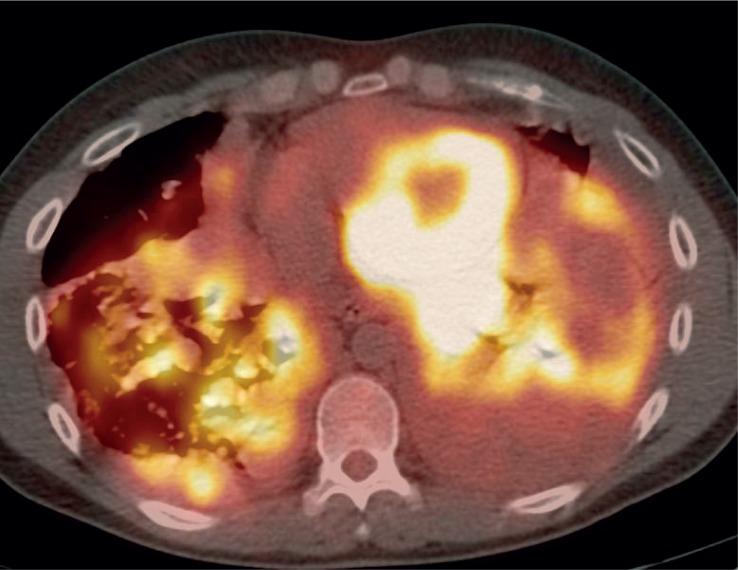

Among 13 patients, 3 died during the timeframe of this study. Nine patients had primary tumor in the lower extremity, and average tumor size was 9.3 cm (range 3.3-18 cm). On MRI, primary tumors were hyperintense on T2, isointense to muscle on T1, and demonstrated peripheral/septal enhancement. Three patients had local recurrence and 12 had metastatic disease, with lung involvement being the most common. Tumor density on contrast enhanced CT ranged from 8.2 to 82.9 Hounsfield unit (HU). FDG-PET/CT imaging was performed in 3 patients. One patient had no FDG avid disease and 2 patients had metastatic disease with standard uptake values (SUV) of 2.8 and 7.4. The patient with intense FDG uptake demonstrated more solid appearing tumor burden and had the shortest survival.

在 13 例患者中,有 3 例在本研究期间死亡。9 例患者的原发肿瘤位于下肢,平均肿瘤大小为 9.3cm(3.3-18cm)。在 MRI 上,原发肿瘤在 T2 上呈高信号,在 T1 上与肌肉等信号,呈外周/间隔增强。3 例患者有局部复发,12 例有转移,其中肺部受累最常见。增强 CT 上肿瘤密度范围为 8.2-82.9HU。3 例患者行 FDG-PET/CT 检查。1 例患者无 FDG 摄取,2 例患者有转移,标准摄取值(SUV)分别为 2.8 和 7.4。FDG 摄取量高的患者肿瘤负荷更呈实性外观,生存时间最短。